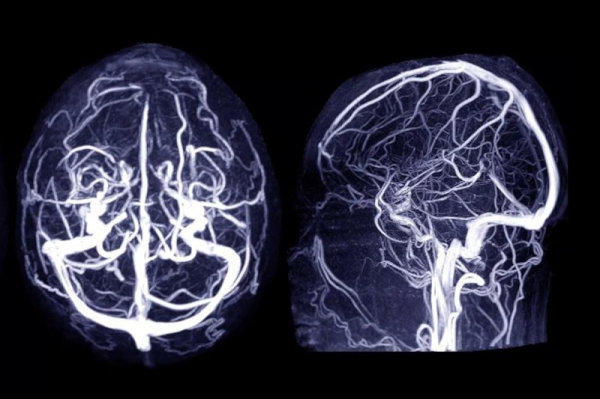

Four common drugs — lisinopril, simvastatin, metformin and tamsulosin — appeared to lower the risk of a brain aneurysm, after accounting for other risk factors. Photo by Adobe Stock/HealthDay News